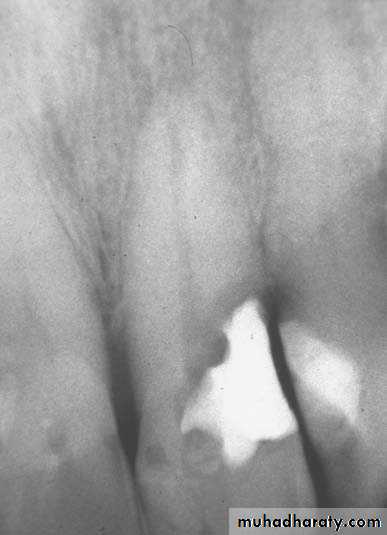

*The No. and curvature of root canals may need modification of outline form & to avoid scarifying of tooth structure.2.Preoperative radiograph: Give great information about status, shape and size of pulp chamber.

Radiographs in Endodontics*Initial radiograph: Diagnosis. *Working length film: Used to determine the length of the canal. *Final instrumentation film: Taken with the final size files in all canals. *Root canal completion film: Taken after the tooth as been temporized. *Recall films: Taken at evaluations.

Requirements of Endodontic Films *Show 4-5 mm beyond the apex of the tooth and the surrounding bone or pathologic condition. *Present an accurate image of the tooth without elongation or fore-shortening. *Exhibit good contrast so all pertinent structures are readily identifiable.